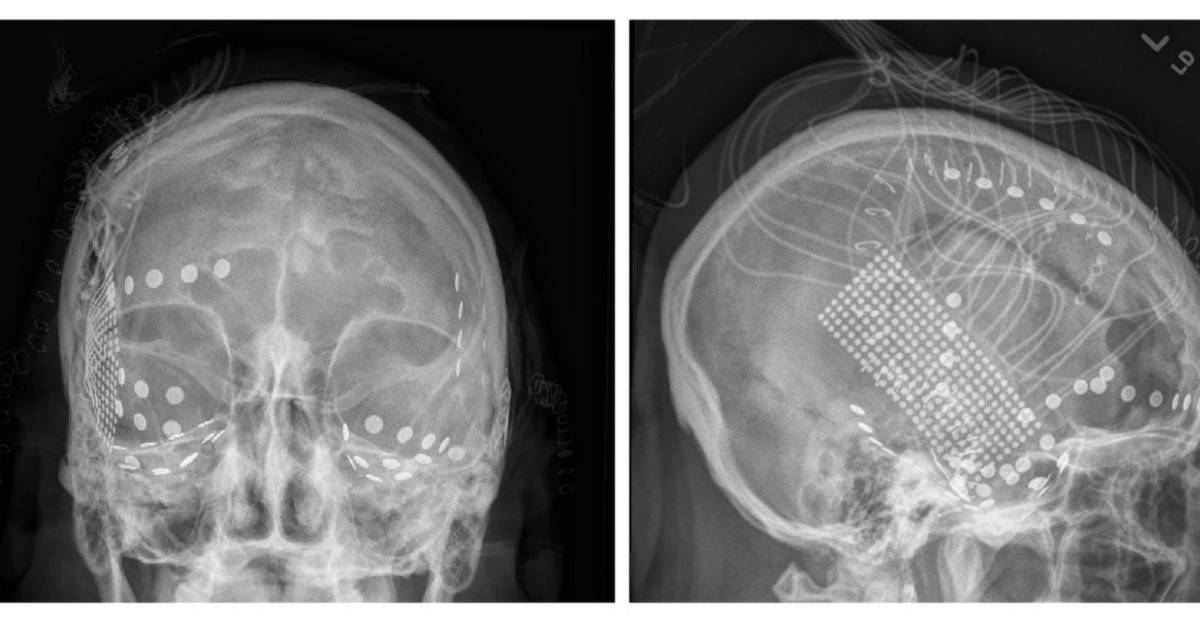

Foto: Fotografías por Peter Brunner

Electrodos registraron señales del cerebro de pacientes con epilepsia mientras escuchaban “Another Brick in the Wall”.

Los investigadores grabaron de los cerebros de 29 pacientes con epilepsia en el Centro Médico Albany en el Estado de Nueva York del 2009 al 2015.

Como parte de su tratamiento, a los pacientes se les implantó una red de electrodos. Esto creó una oportunidad para que los neurocientíficos registraran su actividad cerebral mientras escuchaban música.